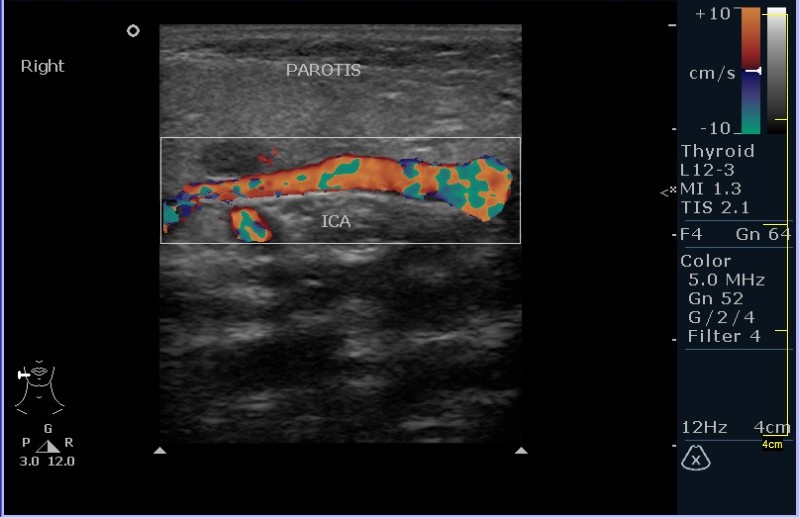

УЗИ области правой околоушной железы и угла нижней челюсти.

Девочка 8 лет, с опухлостью щеки и области правого угла нижней челюсти, резко боезненной при пальпации. В анамнезе (после наводящих вопросов :ugeek: ), визит к стоматологу около месяза назад.